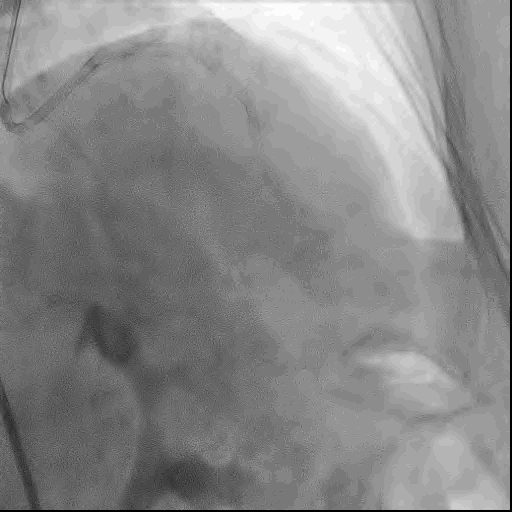

术前冠脉造影

RCA近中段弥漫性狭窄伴钙化,狭窄30-60%,RCA远端发出广泛侧支供应LAD远端